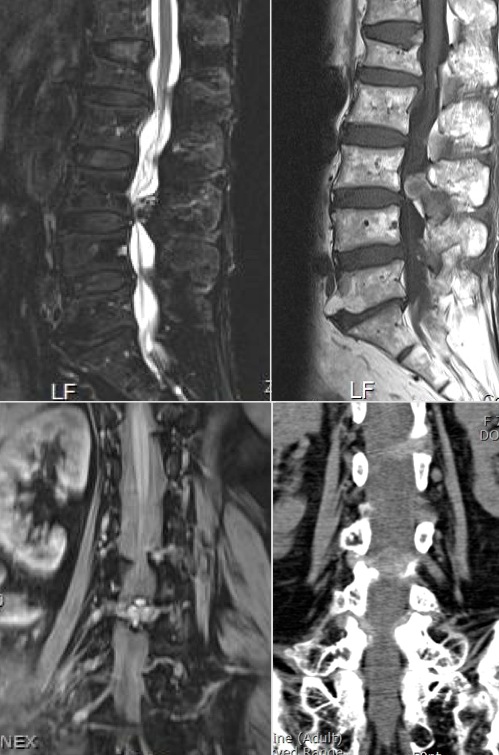

Pain

Courtesy Kyung Jin Suh, MD PhD